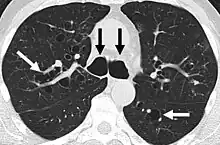

A chest x-ray is abnormal in most patients with bronchiectasis. Computed tomography is recommended to confirm the diagnosis and is also used to describe the distribution and grade the severity of the disease. Radiographic findings include airway dilation, bronchial wall thickening, and atelectasis.[65] There are three types bronchiectasis that can be seen on CT scan, namely cylindrical, varicose, and cystic bronchiectasis.[66]

Bronchiectasis primarily in the middle lobe of the right lung.

Bronchiectasis secondary to a large carcinoid tumor (not shown) that was completely obstructing the bronchus proximally. Dilation of the airways is present.